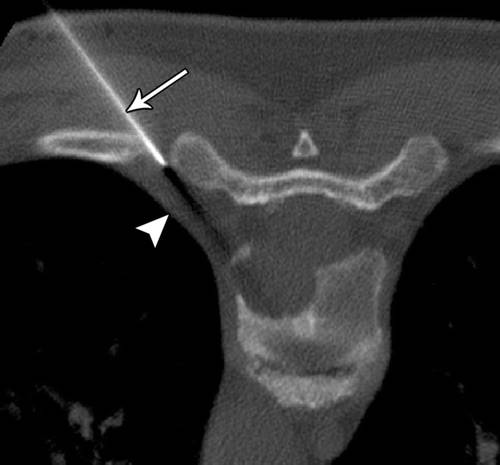

![]()

4/前臂在轴向平面上的示意图。

骨间膜(箭头)分隔伸肌(E)和屈肌(F)隔间。应特别小心不要伤及骨间膜,从而避免多个隔室的污染。R =桡骨,U =尺骨。

5 / 20岁女性桡骨内软骨瘤。

前臂的CT图像显示11号针头(箭头),桡骨(星号)。小心不要穿过骨间膜。